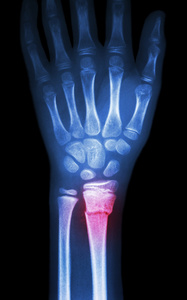

桡骨远端骨折是常见的骨折类型,多发于老年 人群 [1-2]。目前临床治疗以手术为主,掌侧 Henry 入路钢板内固定术是治疗桡骨远端骨折的经典术 式,但该术式需将旋前方肌切开,远期会出现不同 程度的肌肉瘢痕化,影响患者肌肉功能和前臂旋 前功能,因此需尝试保留旋前方肌,对 Henry 入路 掌侧钢板内固定术进行改良 [3-4]。保留旋前方肌改 良 Henry 入路掌侧钢板内固定术骨折复位后钢板从 旋前方肌下方插入进行内固定,治疗效果较好 [5-6]。 本文观察保留旋前方肌改良 Henry 入路掌侧钢板内 固定术治疗老年桡骨远端骨折患者的效果。

1.1  一般资料  选取 2018 年 5 月至 2020 年 11 月 河南省滑县骨科医院收治的 80 例老年桡骨远端骨 折患者进行前瞻性研究。纳入标准:经 X 线确诊为 闭合性桡骨远端骨折;年龄≥ 60 岁;骨折 AO 分 型为 B 型和 C 型;受伤至手术时间在 7 d 内;符合 手术指征。排除标准:合并凝血功能障碍、免疫系 统疾病;合并严重感染;陈旧性骨折;心肺功能差, 不耐受手术;合并精神疾病,难以配合研究;合并 其他部位骨折;依从性差、中途退出。患者及家属 了解本研究内容并自愿签署知情同意书,且研究经 河南省滑县骨科医院医学伦理委员会审批通过(审 批文号:20220106) 。以抽签法随机分为对照组 和观察组各 40 例。对照组男 15 例,女 25 例;年 龄 61~79 岁, 平均(67.32±5.89) 岁; 骨折 AO 分 型:B1型9例,B2型8例,B3型6例,C1型6例, C2 型 7 例, C3 型 4 例。观察组男 16 例, 女 24 例; 年龄 60~78 岁, 平均(67.05±6.33) 岁; 骨折 AO 分型:B1 型 10 例,B2 型 7 例,B3 型 5 例,C1 型6 例,C2 型 8 例,C3 型 4 例。两组一般资料比较, 差异无统计学意义(P>0.05),有可比性。

1.3  观察指标  (1)比较两组术后疼痛评分和前 臂旋转角度。于术后 1、2、3 周采用视觉模拟评分 法(VAS)评估两组疼痛程度;采用前臂旋转关节 角度测量尺测量前臂旋转角度。(2)比较两组骨 折愈合评分。于术后 1、2、3 周拍摄两组腕关节正 侧位 X 线片, 采用 Lane-Sandhu X 线评分法 [7] 评 估骨折生长愈合情况,包括骨形成、骨连接、骨塑 形 3 项 11 个条目, 骨形成:1~4 分; 骨连接:0~4 分; 骨塑形:0~4 分; 总分 0~12 分, 评分越高提 示骨折愈合越好。(3)比较两组术后腕关节活动 度。于术前和术后 3 周测量两组腕关节屈曲活动度、 背伸活动度和尺偏活动度。(4)比较两组术后上 肢功能和日常活动能力。于术后 2、3 周采用上肢 功能障碍评定量表(DASH)评估患者上肢功能, 采用 Barthel 指数评估患者日常活动能力,总分均 为 0~100 分,DASH 得分越低表示上肢功能越好, Barthel 指数得分越高表示日常活动能力越好。(5) 比较两组治疗优良率。术后 3 个月, 患者患肢功能、 握力均恢复正常,关节活动无限制,为优;术后 3个月,患者患肢功能、握力未完全恢复,关节活动 部分限制,为良;术后 3 个月,患者患肢功能无好 转,甚至加重,为差。(6)比较两组术后 1 个月 并发症发生率。